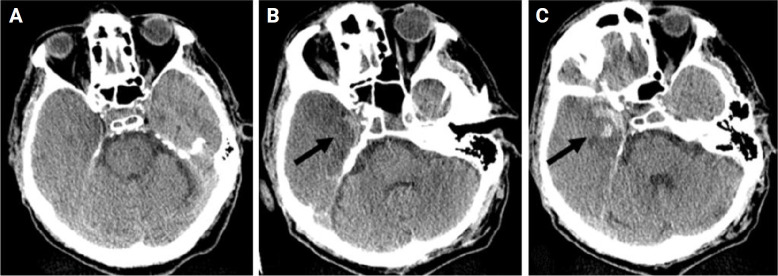

Herpes simplex encephalitis (HSE) is a potentially fatal infection of the brain parenchyma with high mortality rates when left untreated. It typically affects the medial temporal lobe, and patients commonly present with headache, fever, and altered mental status. The combination of clinical findings and brain imaging should raise suspicion, whereas cerebrospinal fluid (CSF) analysis should establish the diagnosis. In a few cases, HSE presents with subacute progression, making diagnosis more challenging. Treatment with acyclovir should begin immediately after HSE is suspected; otherwise, the mortality rate is high. Herein, we present a rare case of HSE with a subacute course admitted to the emergency department because of an episode of syncope with concomitant bradycardia. HSE symptoms developed gradually during the first week after hospitalization. Typical imaging findings, CSF analysis, and polymerase chain reaction results positive for herpes simplex virus-1 confirmed a diagnosis of HSE. The insidious symptomatology of this case led to delayed acyclovir administration and the patient unfortunately died 4 days after diagnosis.

Abstract Image